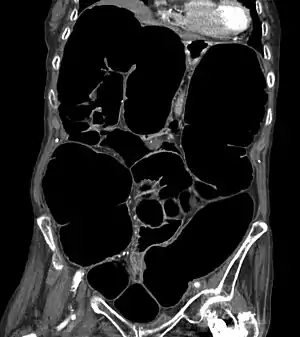

CT-Scan showing a coronal section of the abdomen of an elderly lady with an IPO.

The symptoms of IPO are nonspecific. It is not unusual for patients to present repeatedly and to undergo numerous tests.[4] Mechanical causes of intestinal obstruction must be excluded to reach a diagnosis of pseudo-obstruction. Attempts must also be made to determine whether the IPO is the result of a primary or secondary condition.[13] A diagnostic work-up may include:[23]

• CT-Scan showing a Cross-section of the abdomen of an elderly lady with an IPO.